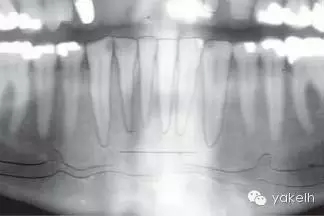

¤¤全景片以及根尖片可用于評估骨缺損、周圍的牙列以及局部解剖形態(tài)。計算機(jī)斷層攝影(CT)對骨缺損的三維觀察十分有用,也能用于評估口內(nèi)供骨區(qū)的情況??山Y(jié)合使用種植設(shè)計軟件與CT掃描,更加精確地評估患者所需重建的骨量。使用計算機(jī)掃描制備頜骨的立體光刻模型,以制訂進(jìn)一步計劃。臨床醫(yī)生通過對架研究模型及診斷蠟型的研究分析,來把握牙槽嵴形態(tài)與預(yù)期修復(fù)結(jié)果的關(guān)系[7]。它們也可用于CT掃描中X線模板的制備[8]。該模板阻射影的輪廓,提示了修復(fù)體在殘余牙槽嵴斷層掃描的位置(圖13.1,圖13.2)。這有助于決定所需移植骨的大小以及取骨的部位。在骨移植手術(shù)中,設(shè)計預(yù)期修復(fù)體位置的模板,對于移植物植入位置的確定以及完成骨移植的要求也是很有用的。

圖13.24 全景片提示切牙管的位置。